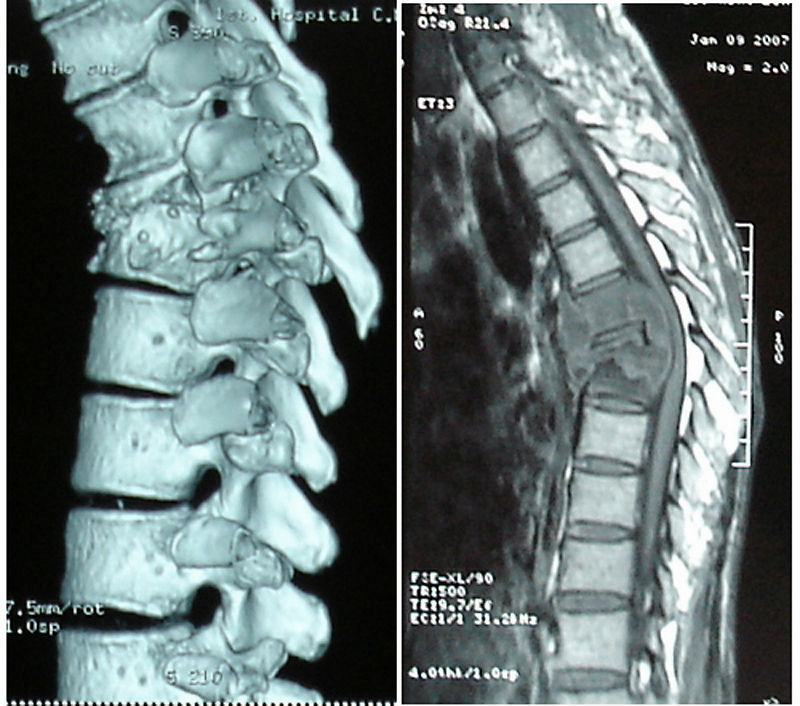

骨结核可分为以以下几类,脊柱结核(腰椎结核 胸椎结核),髋关节结核,肩关节结核,踝关节结核,肘关节结核,腕关节结核,膝关节结核。其中以腰椎最为突出,占总数的40%,而且腰椎结核的并发症也是最严重的,最严重的就是截瘫,给患者带来一生的痛苦。